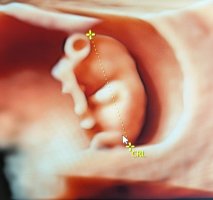

Ultralydbilder ✨